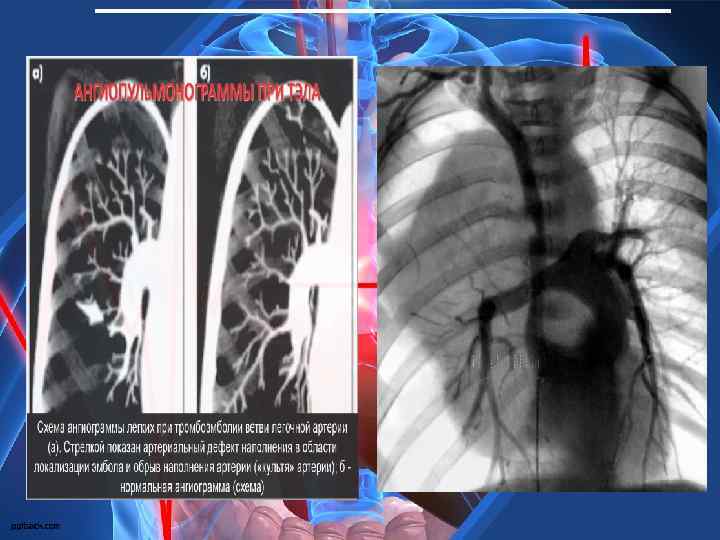

Селективна ангіопульмонографія є «золотим» стандартом діаг-ностики та дозволяє виявити: • збільшення діаметра ЛА; • повну або часткову відсутність контрастованих судин легені на боці ураження (“ампутація” тіні ЛА або її гілок – симптом “мертвого або обрубаного” дерева), залежно від рівня оклюзії; • деформацію легеневого рисунка